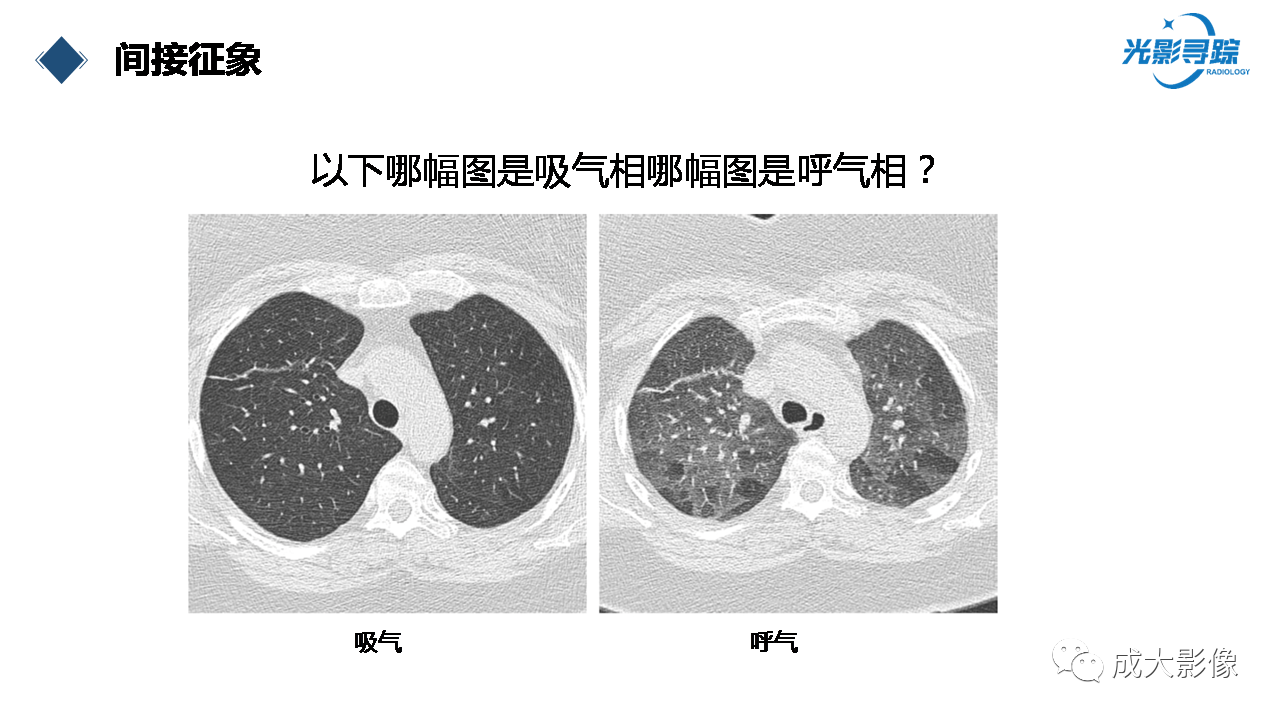

细支气管炎——普通放射科医生的实用策略